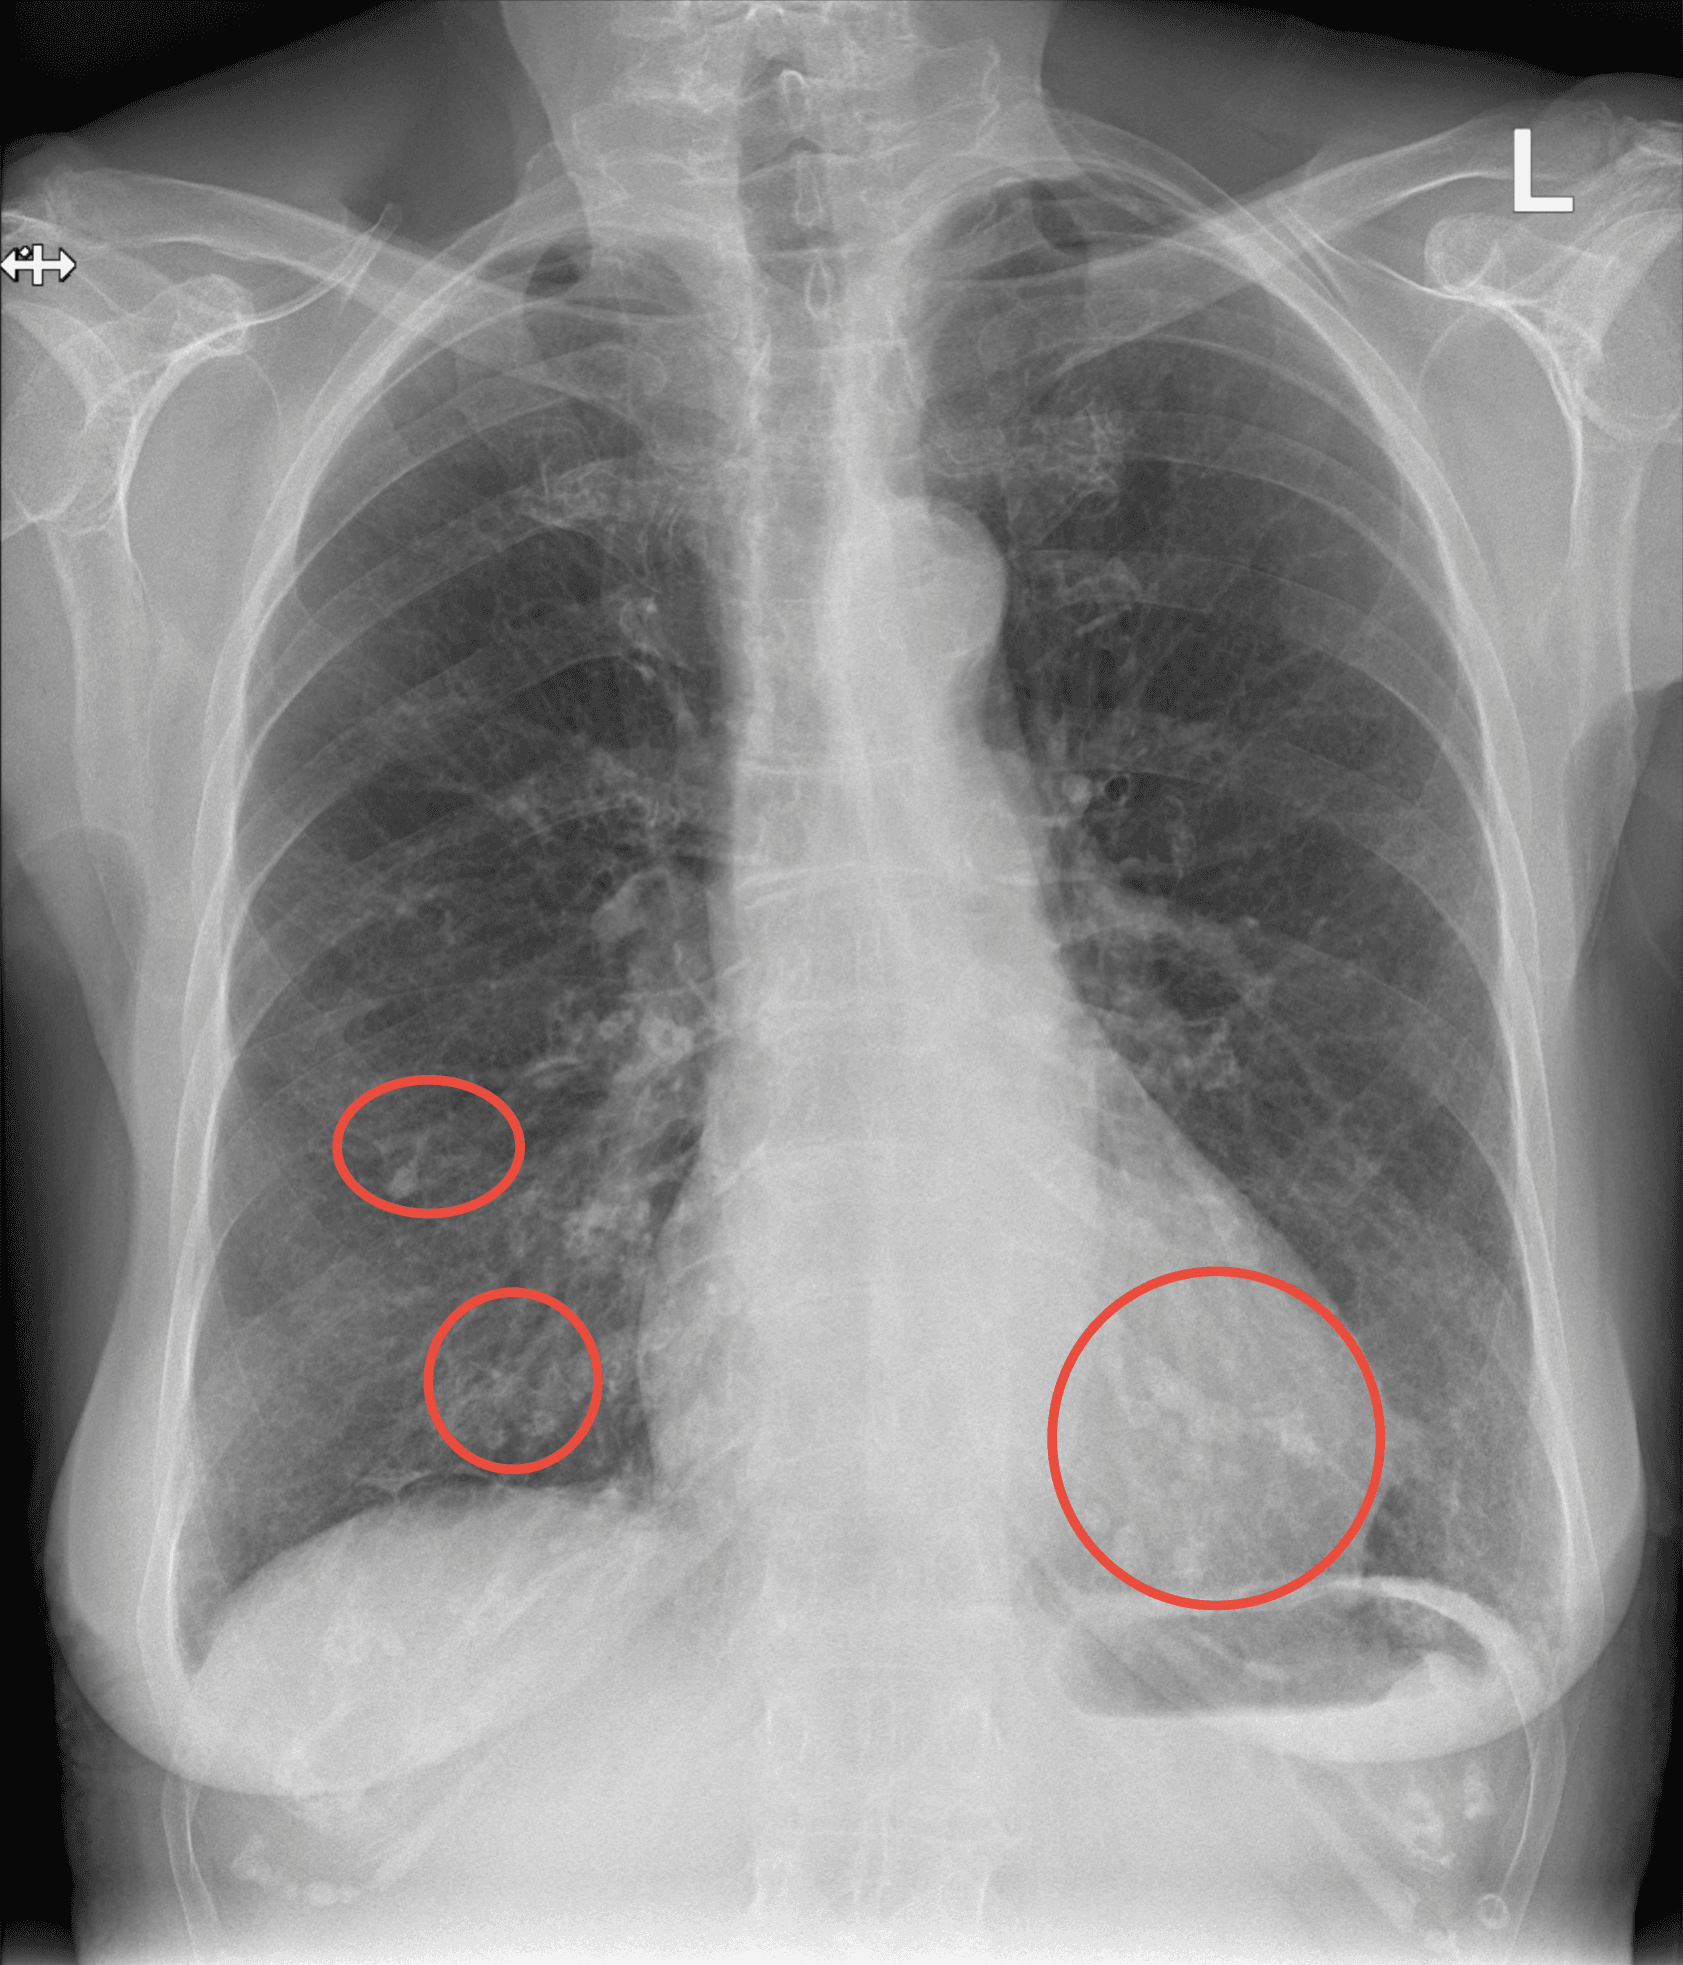

98% certainty

Medusa detected Emphysema in the lungs